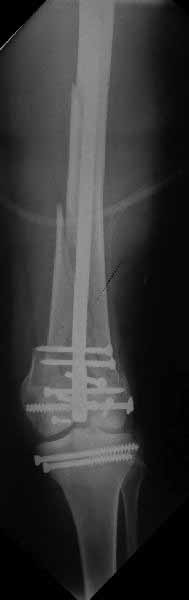

Ну зачем же так. Всё-таки считается "золотым стандартом". Во вложенном файле коллаж из сохранившихся фотографий одной из операций. Всё сделано закрыто и без ЭОПа.

Ответ на эту часть Вашего поста – вложенный файл. Больная оперирована неделю назад по поводу открытого перелома дистального эпиметафиза бедренной кости. После операции она идёт в рентгенкабинет для выполнения послеоперационной контрольной рентгенографии, представленной на слайдах 10 и 11. Узнав, почему её фотографируют, просила передать Вам, Антон, привет.

В приложении пример недавней операции, C3, открытая репозиция, фиксация мыщелков спицами и винтами, ретроградный синтез большеберцовым гвоздем 10,5 мм диаметром, винты 5 мм.

Коллеги, извиняюсь за задержку с результатом. Через медиальную артротомию обнажили н/3 бедра, отрепонировали внутренний мыщелок, затем по нему сопоставили суставную поверхность бедра с латеральным мыщелком.

Больная выписана в ортезе с регулируемым углом сгибания в колене, с рекомендациями через 3 нед. удалить спицы и начать разрабатывать сустав.

По прямому снимку репозиция удалось, поздравляю! А с латеральной стороны подозрение на флексионный компонент латерального мыщелка остается, а снимок получился косым, надо было бы повторить.

Выбор имплантов не совсем удачный, подкожно выступающие болты в мыщелках вскоре могут привести к проблемам. Вместо солитарной фиксации болтом-стяжкой дистально можно было бы добавить пару винтов, которые создали бы ротационную стабильность и межфрагментарную компрессию.

Возможно, есть скрытый замысел, неочевидный для нас - не понятны латерально оставленные спицы. Спицы возможный очаг вторичного осложнения, и, тем более у взрослых, тонкие спицы не создают адекватную фиксацию.